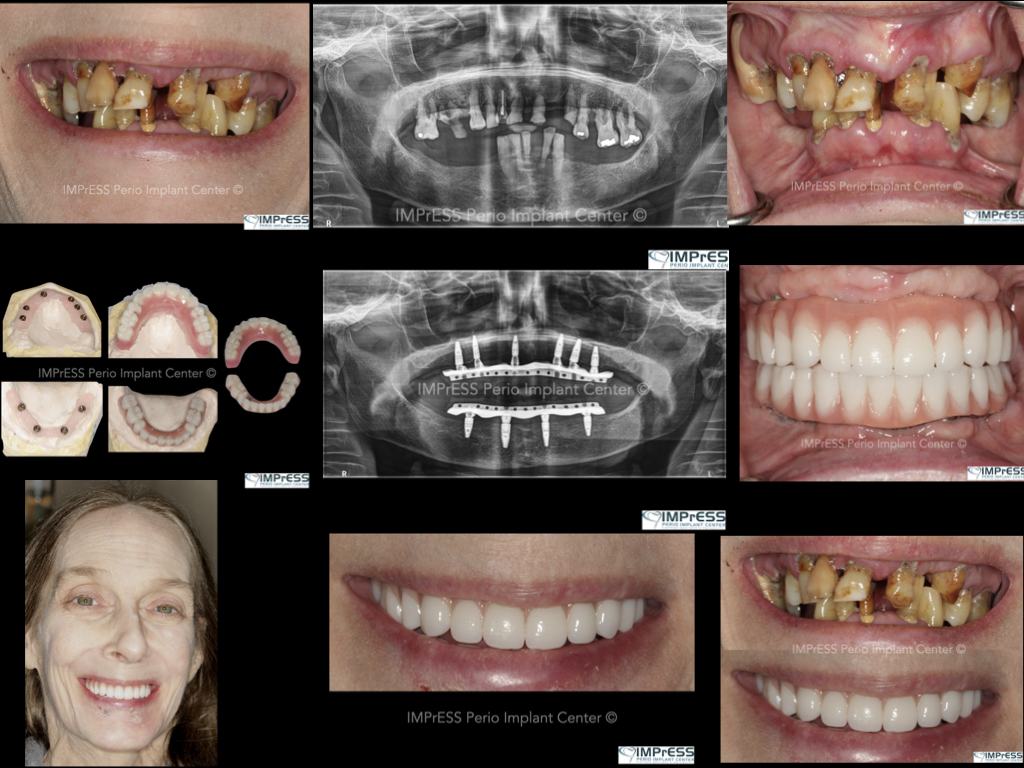

Full Mouth Reconstruction with Fixed Implant Bridge – All on X